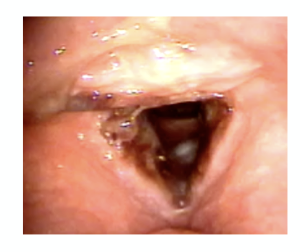

What condition is this? How do you confirm findings?

Paradoxical Vocal Fold Motion (PVFM)

Diagnosed by clinical suspicion. Confirmed by endoscopy. In mild intermittent cases, often only reassurance is needed.